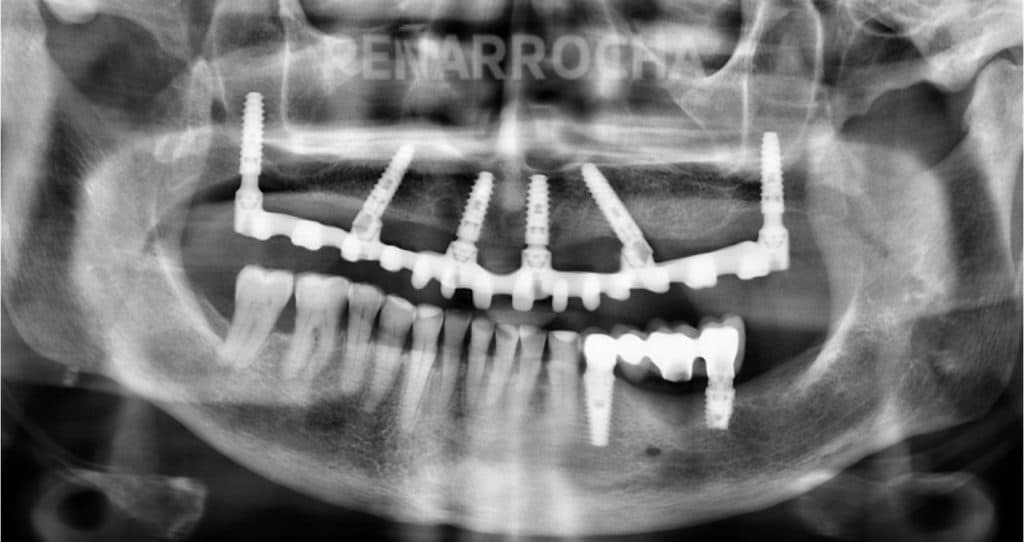

¿Es posible tener dientes nuevos en un solo día? En la actualidad sí, gracias a los últimos avances en implantología dental. Los implantes dentales en un día, o implantes de carga inmediata, permiten recuperar la funcionalidad y la estética de tu boca en tan solo 24 horas, sin tener que esperar meses para obtener el […]